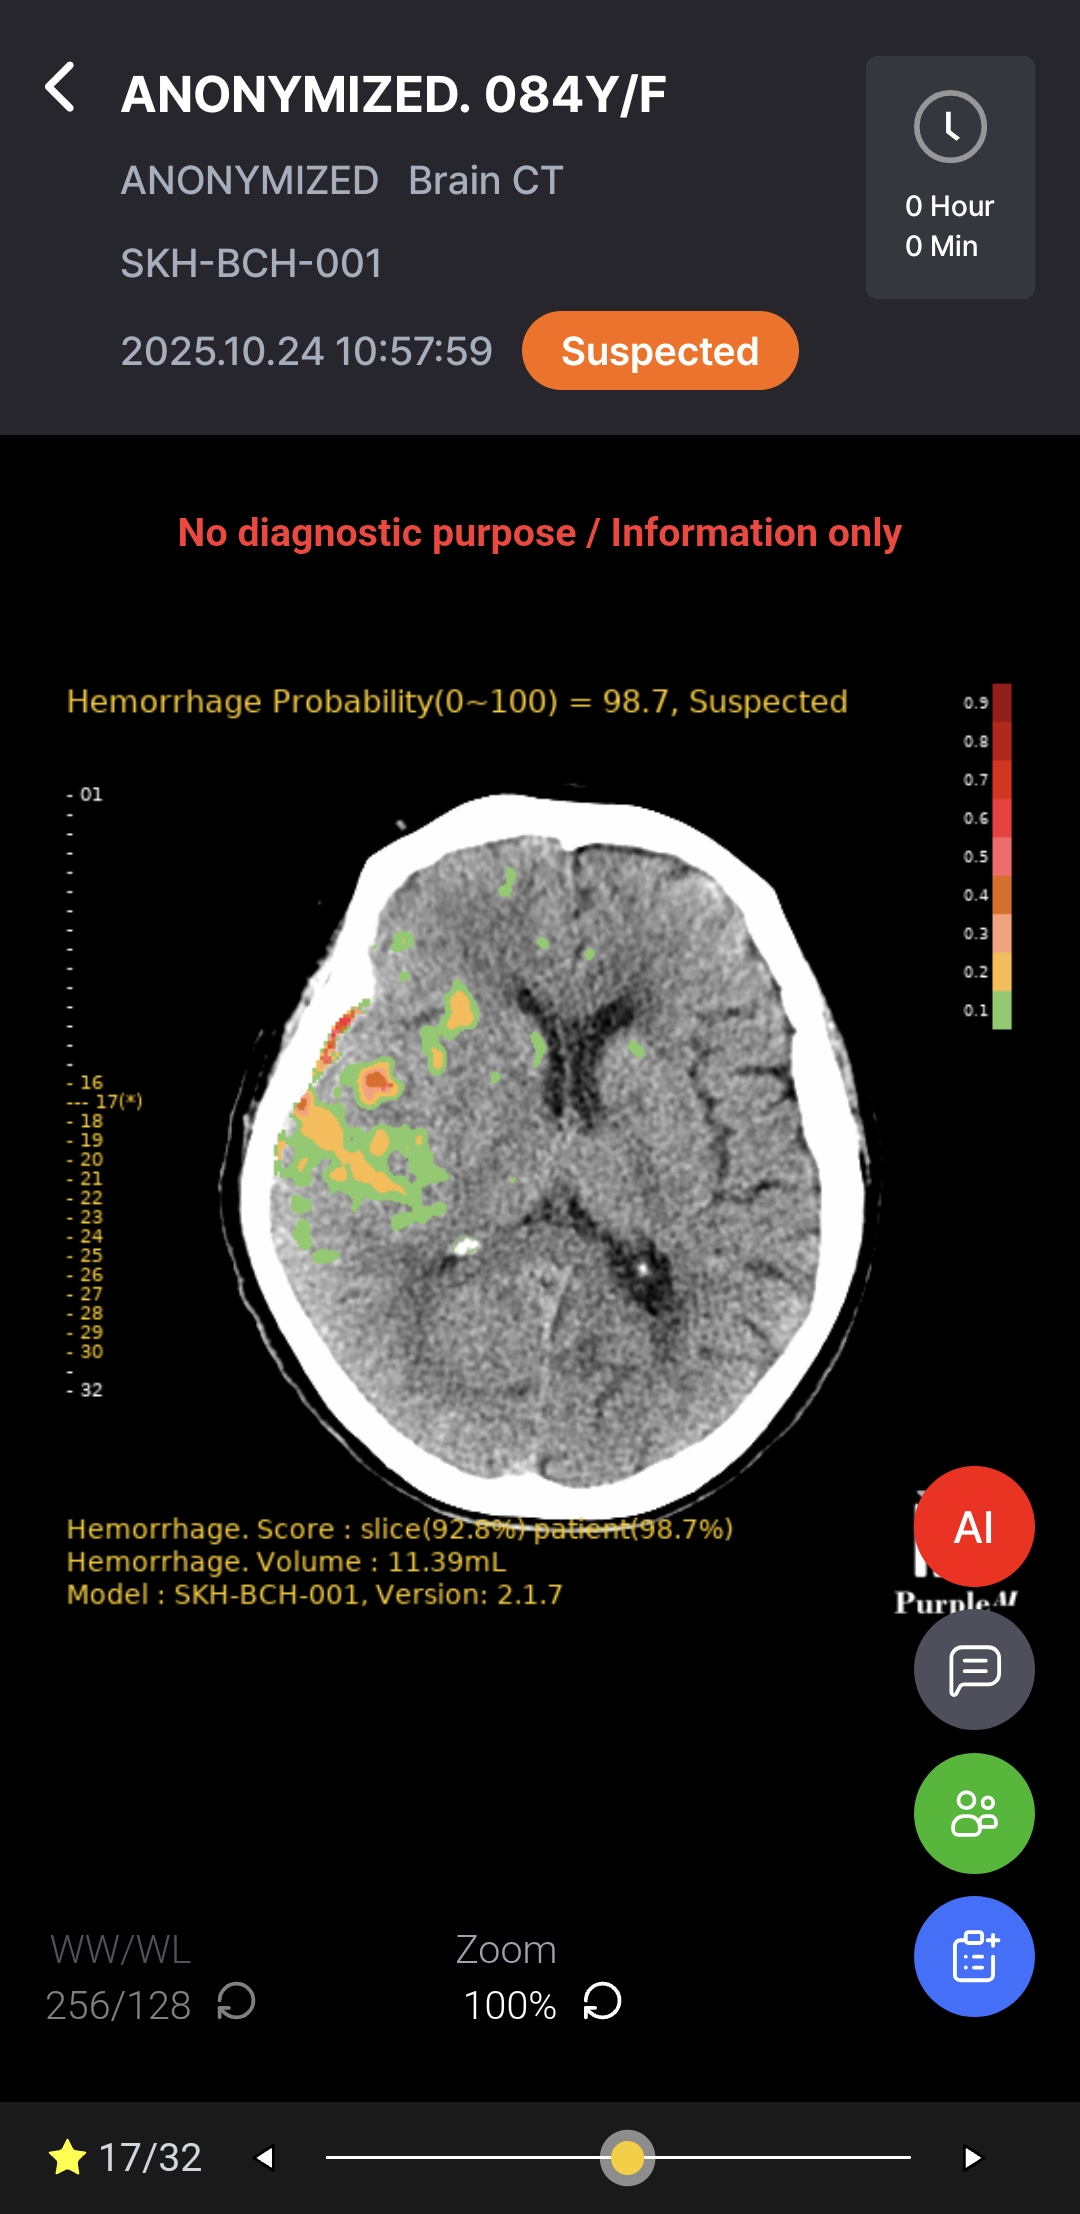

Download BrochureAI-powered diagnostic support for rapid, accurate detection and localization of brain hemorrhages on non-contrast CT, with ROI visualization and volume quantification to help radiologists assess hemorrhagic regions.

Notifications & AI DICOM Viewer